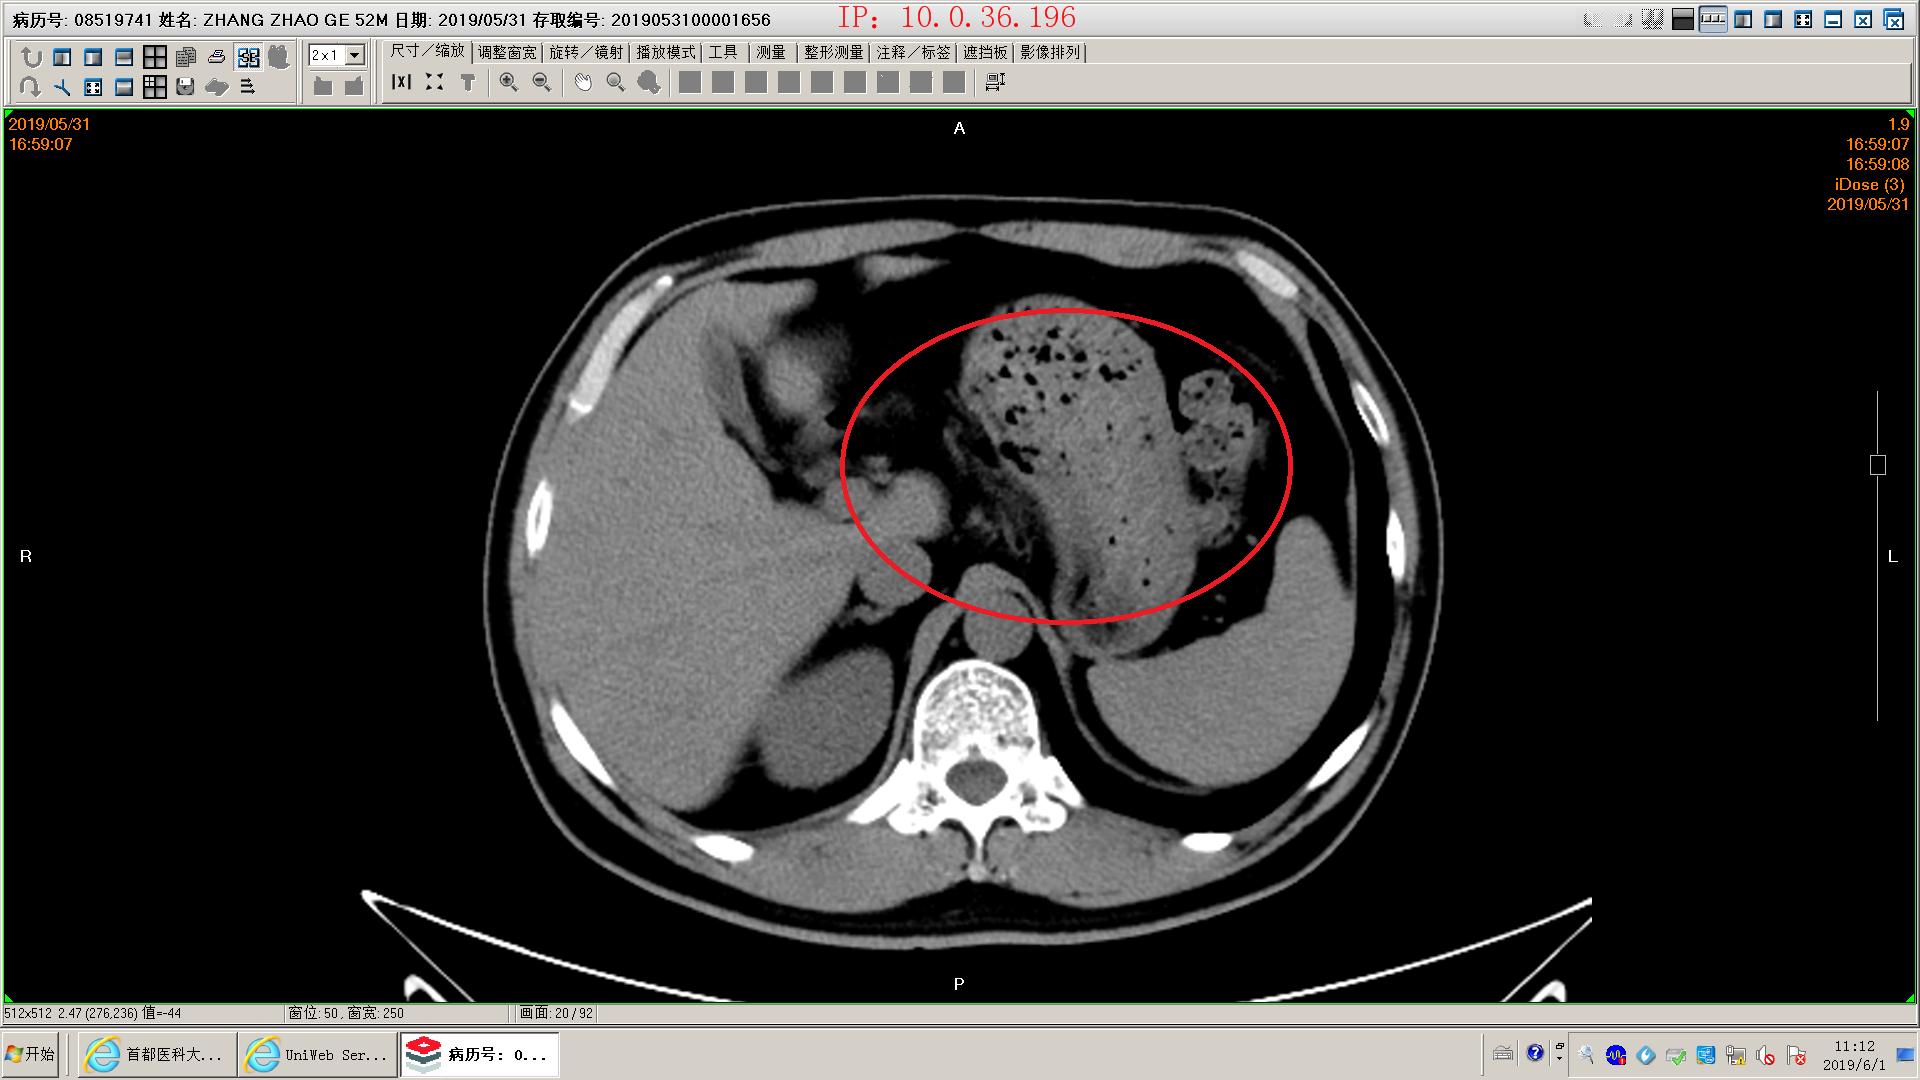

下面是一例胆源性胰腺炎影像学和化验表现,这个病人没有脏器功能不全,胰腺坏死不明显,周围没有明显积液,还不是重症胰腺炎。虽然有可疑胆管结石,但是没有黄疸,我们会在做核磁mrcp证实一下结石的位置。患者胃里面有一些残存的食物,我们会用胃管做胃肠减压,有助于胃肠道休息恢复;肠道里面积存的粪便也比较多,肠鸣音听不到,通过肥皂水灌肠促进肠道蠕动排除,有助于胃肠道功能恢复。然后给予生长抑素抑制胰酶分泌,禁食水补液,消炎治疗。

可疑胆总管结石

胰腺模糊渗出,坏死不明显

胰腺间隙模糊

胃内有残余食物